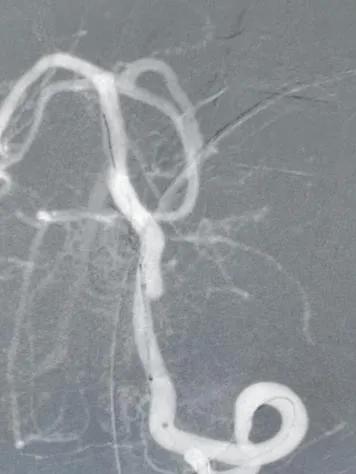

连接高压肝素盐水冲洗装置,6F导引导管在超滑导丝引导下超选进入左椎动脉入路段,行左椎动脉3D旋转造影并选取工作位,见左椎动脉V4段夹层动脉瘤,瘤颈约0.9cm,载瘤动脉约3.7mm(见下图)。

术中诊断:左侧椎动脉V4段夹层动脉瘤。